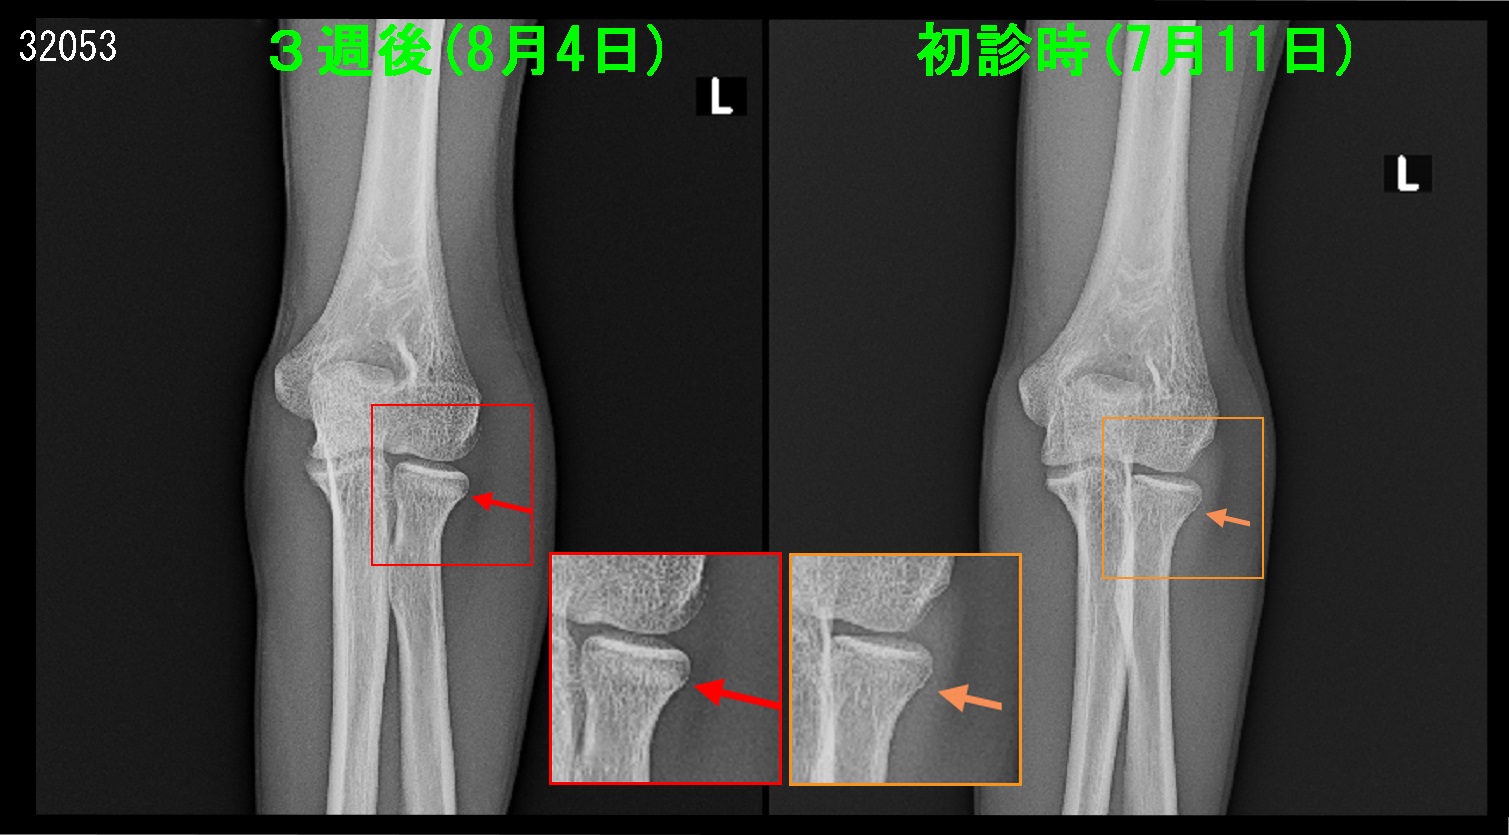

15才高校1年のバレーボールの男子生徒です。令和4年7月3日自転車で転倒し、左肘を打撲しましたが、部活の練習を続けていたところ、左肘痛が続くということで7月11日に当院を受診されました。日常生活では痛みはないということでした。

15才男 初診Xp.jpg

レントゲン像では異常はみられませんが、橈骨(親指側の骨)の関節側(赤丸部分)に圧痛を認めました。私はおそらく骨折があると思われるので、MRI検査で確認することを勧めました。

15才男 3週後Xp.jpg

3週後のレントゲン像では赤矢印の部分に骨折治癒のための新しい骨形成(仮骨形成と言います)が確認され、治療経過観察を終了しました。